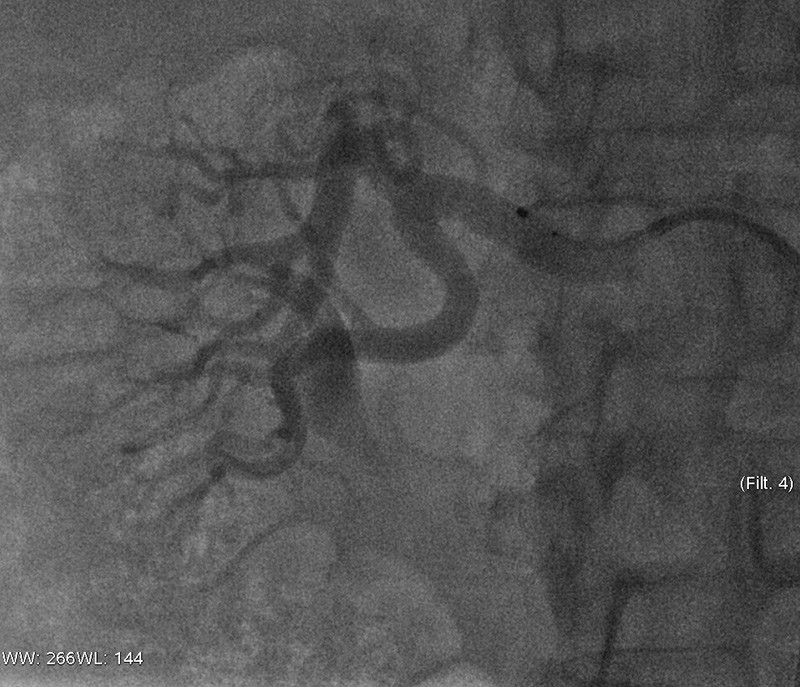

Det er utviklet flere typer intervensjonsmetoder for renal denervering. Den hyppigst brukte i studier er Symplicity Catheter System (10). Ablasjonskateteret, som er koblet til en radiobølgegenerator, føres til nyrearteriene via en perkutan inngang i a. femoralis communis. Ablasjon utføres via en elektrode på enden av kateteret (fig 1). Ablasjonstiden er 2 minutter på hvert punkt i arterien.

For å få best mulig resultat, med optimal nervedestruksjon, gjøres punktvise ablasjoner i spiralform longitudinalt i nyrearterien. Man starter distalt, og etter hver ablasjon trekkes katetret ca. 5 mm og roteres (10). Totalt uføres 4 – 8 ablasjoner per nyrearterie, avhengig av arteriens anatomi og lengde (fig 2). Hvert ablasjonsområde har en diameter på 5 mm, derfor vil en slik gjennomføring med stor sannsynlighet treffe nervefibrene. Umiddelbare komplikasjoner har knapt vært rapportert, men den langsiktige effekten på nyrearteriene er ukjent. Katetre med multiple elektroder samt bruk av ultralyd, nevrotoksiske medikamenter og kryoablasjon er metoder under utvikling som vi kanskje vil se mer av i fremtiden (10).